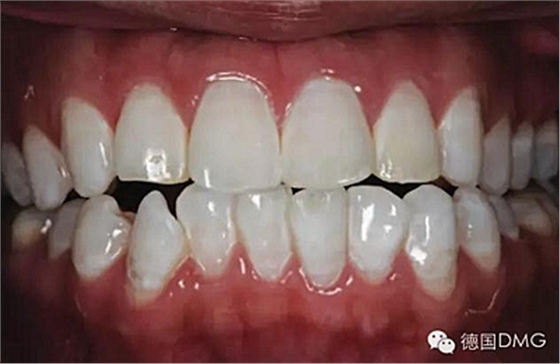

一28歲女性患者來我院修復(fù)科就診,主訴為前牙嚴(yán)重的牙齒著色和缺損十余年,要求改善牙齒的美觀。臨床檢查表明該患者有重度氟斑牙,極大的影響了前牙美學(xué)。

5、由于氟斑牙存在釉質(zhì)礦化不全等問題,家庭漂白兩周后,使用標(biāo)準(zhǔn)的樹脂滲透技術(shù) (Icon, DMG Products, Hamburg. Germany) 來預(yù)防釉質(zhì)齲。最后,徹底改變患者的前牙美學(xué),并在一年后仍保持穩(wěn)定。